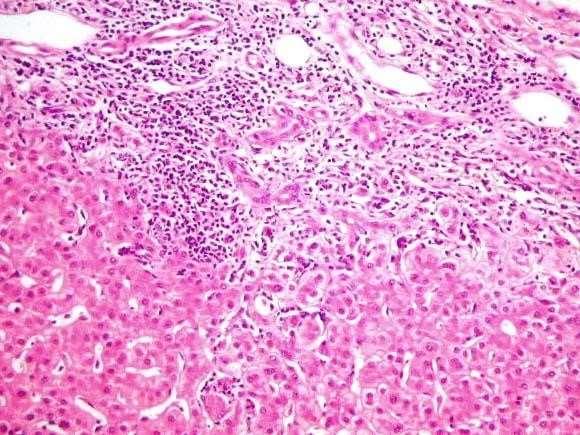

Cholestatic disease

• PBC: Middle ages female, granulomas and lymphocytic infiltrates in portal tract

• PSC: Assoc with IBD more UC, less CD